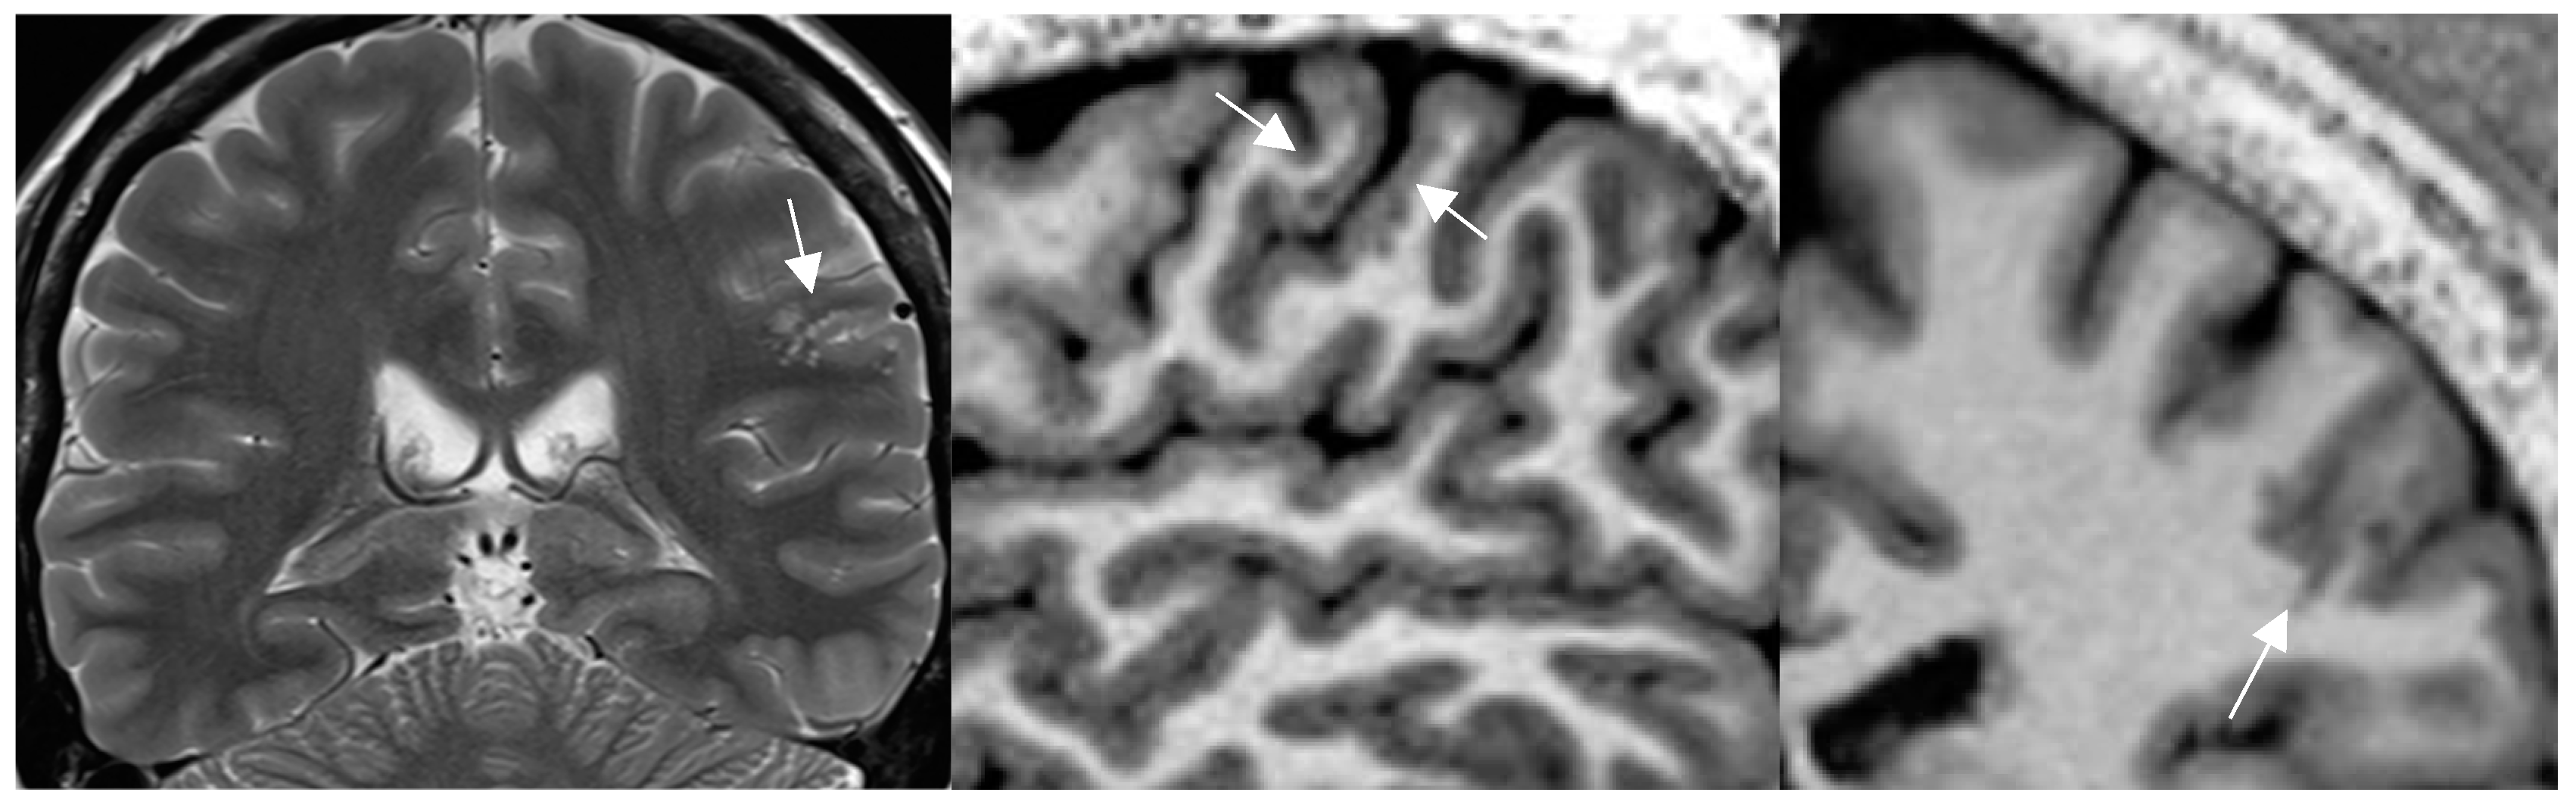

4.1. Pathologies Likely to Be Missed on Brain MRI in Patients with Epilepsy

4.2. A standardized Epilepsy Specific Protocol Provides Superior Diagnostic Yield

4.5. New MR Sequences Display Tissue Properties for Improved Visualization of Lesions

4.6. Postprocessing by Morphometric Analysis Improves Focal Lesion Detection Beyond Visual Analysis

4.7. Postprocessing by Quantitative Analysis of Signal Intensity, Volumetry Enhances Temporal Lesion Identification

4.8. Postprocessing by 3D Surface Rendering Technique to Improve Comprehension of Superficially Located Lesions

4.9. MR Fingerprinting Exploits Tissue Properties to Reflect “Activity“ of a Lesion

4.12. New Entities: Knowledge Shapes Perception